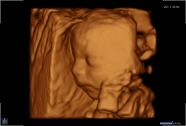

3D/4D-Ultraschall für Schwangere

Seit März 2019 steht ein neues 3D/4D-Ultraschallgerät für faszinierende Eindrücke von Ihrem Baby zur Verfügung.